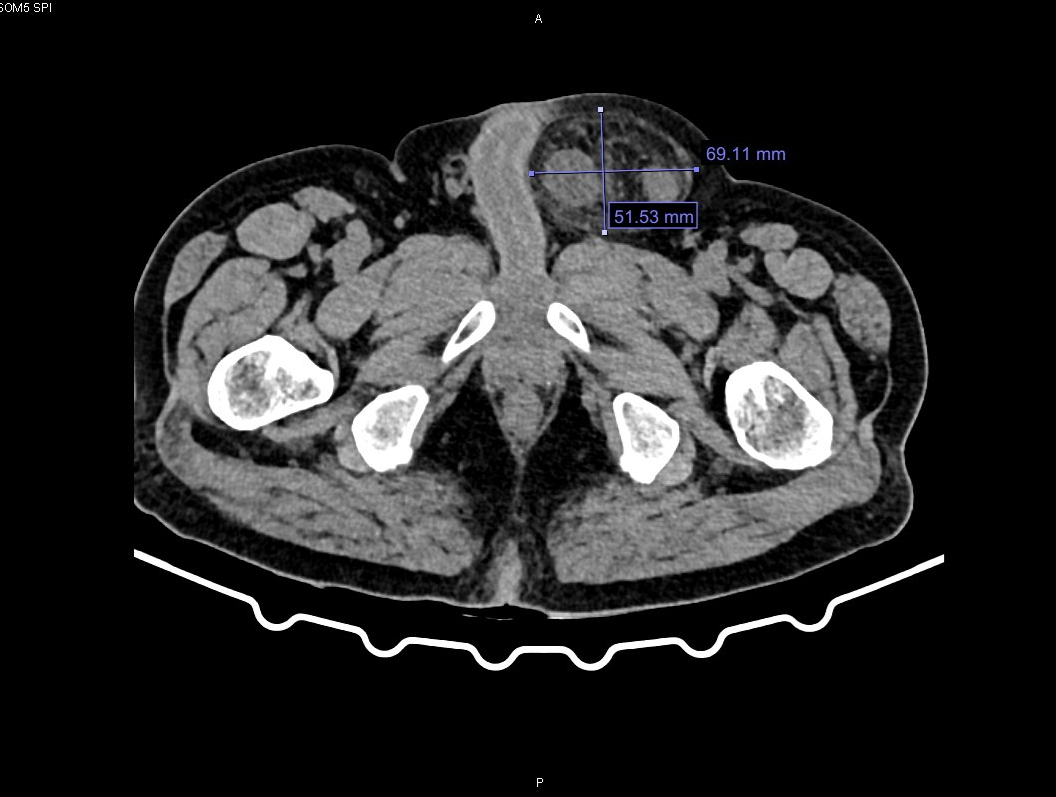

Sau khi thăm khám và chụp cắt lớp vi tính, các bác sĩ chẩn đoán bệnh nhân bị thoát vị bẹn trái nghẹt. Quá trình hội chẩn bác sĩ đánh giá, đây là biến chứng phức tạp, nguy hiểm của thoát vị bẹn do ruột bị chui xuống lỗ thoát vị và kẹt lại gây tắc nghẽn, thiếu máu nuôi. Sau đó, bệnh nhân được chỉ định mổ cấp cứu bằng phương pháp nội soi, nhằm giải phóng khối thoát vị và xử trí tổn thương.

Qua đường rạch nhỏ 1cm ở thành bụng, phẫu thuật viên đưa camera vào kiểm tra phát hiện trong ổ bụng có nhiều dịch tiêu hóa lẫn nhiều giả mạc. Biểu hiện tình trạng viêm nhiễm nặng, lỗ bẹn phải bình thường, lỗ bẹn trái có đại tràng chui vào gây nghẹt. Khi giải phóng khối thoát vị, ekip nhận thấy đoạn đại tràng sigma đã bị hoại tử đen.